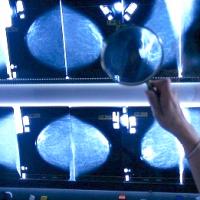

A mammográfiás vizsgálatok során a legnagyobb kihívást a mell szöveteiben a rákmegelőző állapotot jelző mikrokalcifikáció detektálása jelentette, amelyek azonosítása roppant nehéz feladat, hiszen alig különülnek el képi jellemzőikben az őket körülvevő szövetektől – tudhatjuk meg a Syracuse Egyetem közleményéből, melyet a Science Daily idéz.

A Hao Chen professzor vezette kutatócsoport munkájának köszönhetően a mammográfia jóval pontosabban képes felderíteni a daganatos elváltozást, ráadásul a tesztek során 36 %-kal csökkent az álpozitív eredmények előfordulása is.